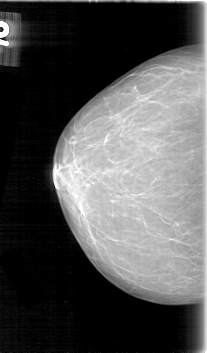

D_4060_1.RIGHT_CC

RIGHT_CC LINES 5281 PIXELS_PER_LINE 3091 BITS_PER_PIXEL 12 RESOLUTION 43.5 NON_OVERLAY